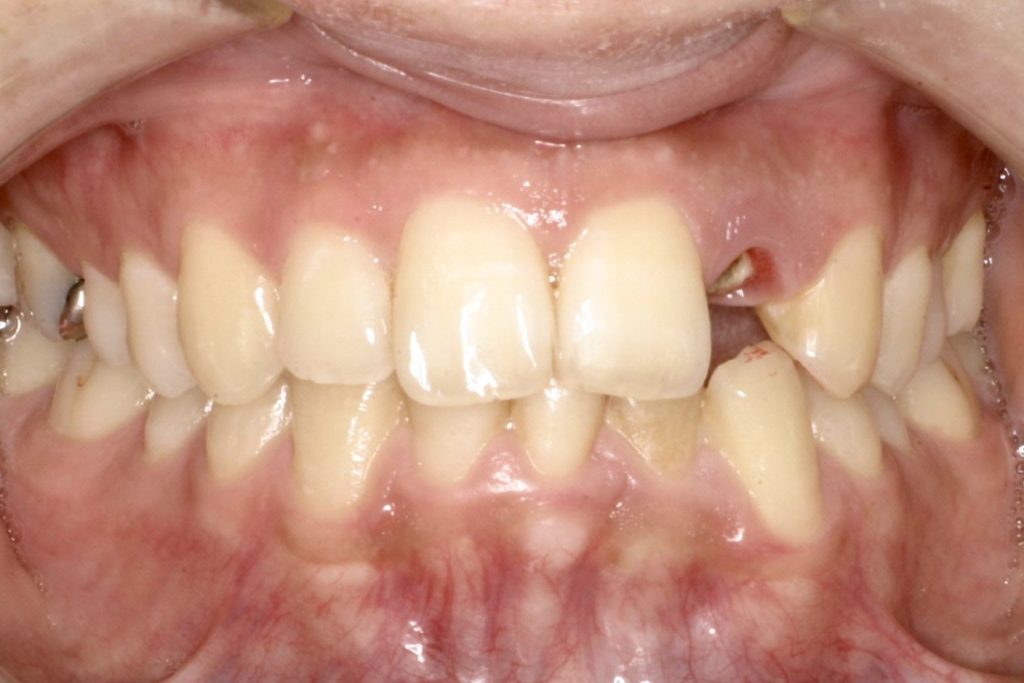

インプラントの症例1)

Before

After